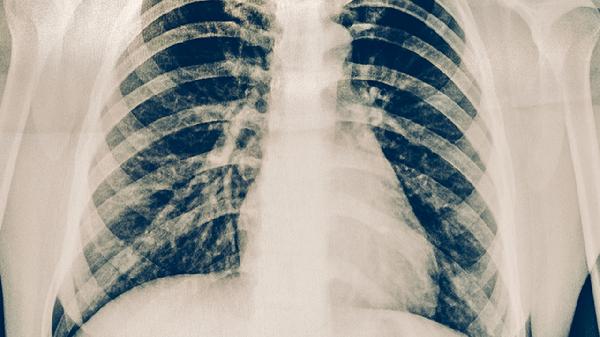

肋骨骨折了吃什么好得快 肋骨骨折多吃这些食物

肋骨骨折患者可以适量吃高蛋白食物、高钙食物、富含维生素D的食物、富含维生素C的食物、富含锌的食物等,也可以遵医嘱使用接骨七厘片、伤科接骨片、骨肽片、碳酸钙D3片、阿法骨化醇软胶囊等药物。建议及时就医,积极配合医生治疗,在医生的指导下服用合适的药物,并做好饮食调理。